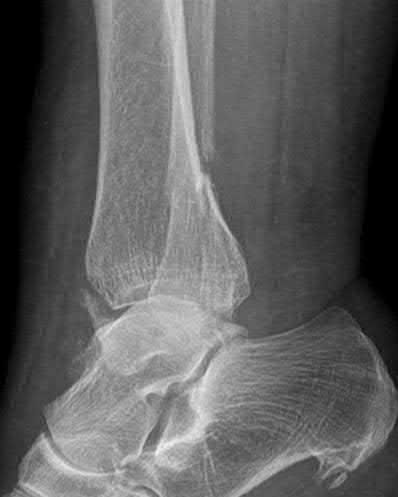

Figure A is an AP radiograph of a posterior knee dislocation. Figure B is a lateral showing the same injury.

Knee dislocations are associated with popliteal artery injury in 18-45% of cases and range from intimal tears to complete transection. Amputation rates of 85% have been reported if revascularization is delayed greater than 6 to 8 hours.

Neurologic injury occurs in 15-40% of cases and is most common after posterolateral dislocation. The peroneal nerve is more commonly injured.

Rihn et al. reviewed the acutely dislocated knee. They recommend a vascular consult if pulses are weak, or ABI is compromised. They warn that in arterial injury, pulses, temperature and capillary refill can be normal. If the limb remains ischemic, surgical exploration and revascularization is indicated.

Medina et al. systematically reviewed neurovascular injury after knee dislocation in 862 patients. Vascular injury rate was 18%, and nerve injury rate was 25%. Repair was performed in 80% of vascular injuries, and amputation in 12%. The most vascular injury was seen in KDIIIL injuries (32%) and posterior dislocation (25%).